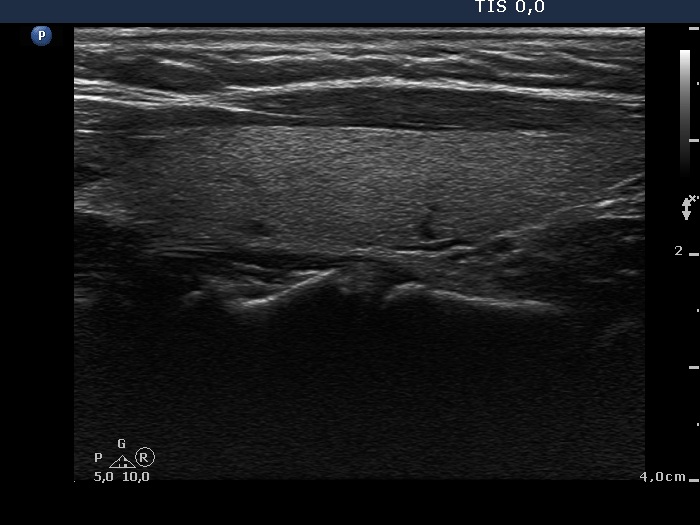

Halo sign and vascular pattern of nodules - case 738 (ultrasonographic picture 5)

Left lobe, longitudinal scan.